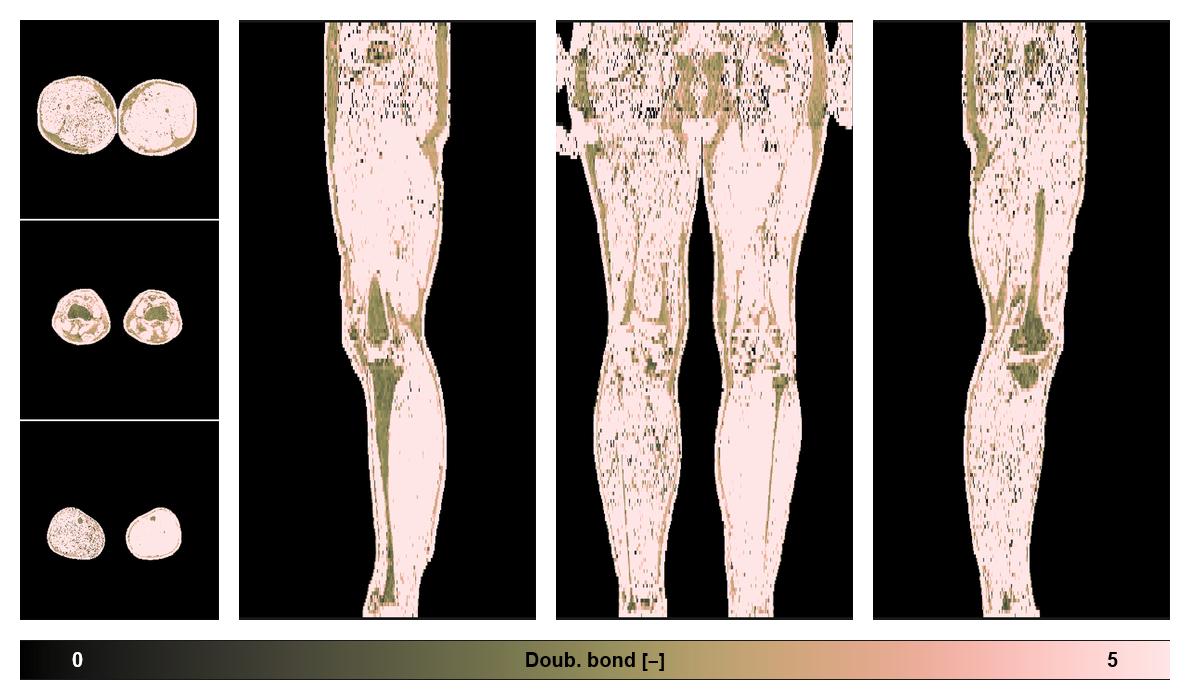

• Number of double bonds in subcutanious fat

Number of double bonds in subcutanious fat.